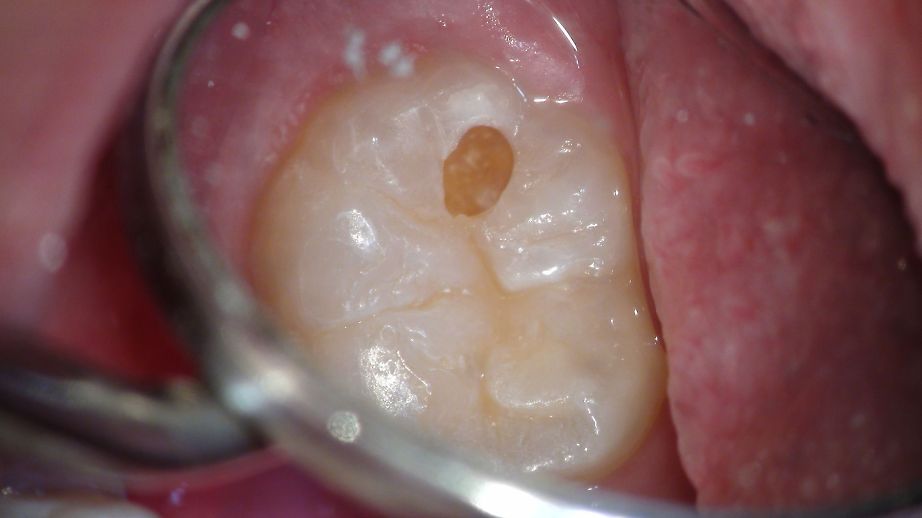

何年も予防健診に来てくれている18歳の男の子。

きれいな歯ですね。

しかし!!!

むし歯でした・゜・(PД`q。)・゜・

ほら、ここ!・・・・・ってわかりませんね。

歯医者さんはこれを見て、むし歯って判断するんですね。

で、開けてみたら、予想以上に進行していた。・゚・(*ノД`*)・゚・。

ダイアグノデントで数値が安定していなかったそうです。